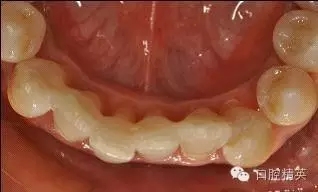

治療后:炎癥得到控制,牙周袋已消除,松動度有所改善。

牙周固定后: